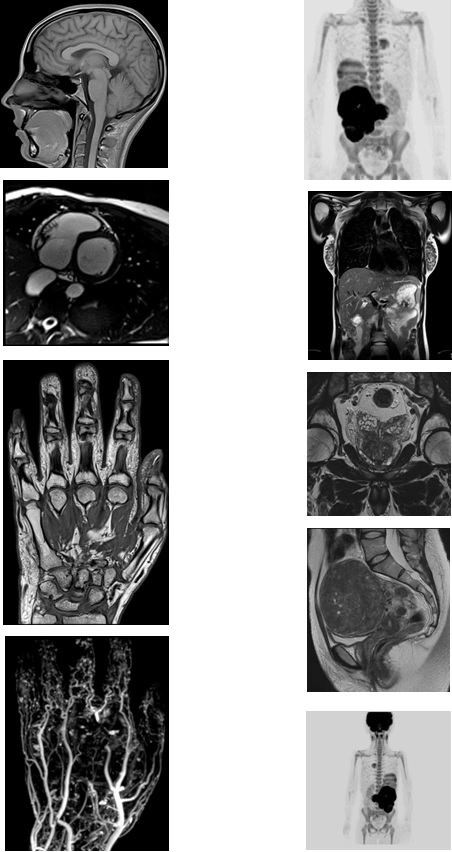

西门子MAGNETOMAera 1.5T纪元四度磁共振可进行神经系统、脊柱、四肢关节、腹部、心脏、血管等全身各个系统的不同疾病的检查,而且能进行波谱分析,对肿瘤的性质鉴定有很高临床价值。对CT无法发现的超早期脑梗塞病变具有无可替代的作用,能发现发病后几分钟内的病灶,为挽救患者生命和改善预后、减少致残率赢得时间,必将进一步提升诊疗水平,为临床诊断提供更有力的硬件支持,为广大患者带来福音。